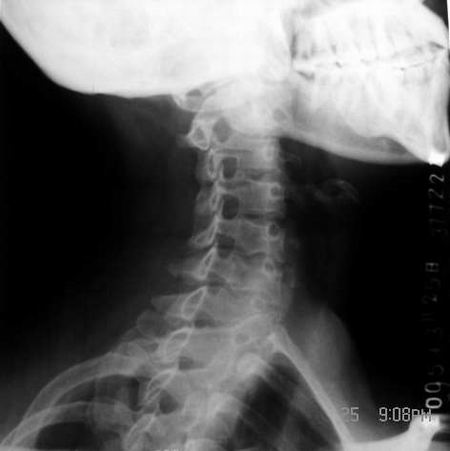

标题: X0220:颈椎 正常还是变异

女 55岁 颈部不适一周余

第七颈肋.

第七颈肋

正常的吧,没有颈肋啊。

无第七颈肋,正常.[emb10]

是颈肋!相片不是很清楚.

颈7横突(右侧)过长,考虑颈肋。

第7椎右缘影系伪影(头发辫子)大家仔细看:从左上斜向右下都有这样的影象喔!

确实有颈肋不过发育的较短小而已。

每个锥体前侧全透亮啊 没见过

谢谢向医生,本人以为椎前缘类圆形透光区存在“问题”,但现在想可能因投照关系,横突相重所致。[emb18]

第7颈椎横突不长,谈何颈肋